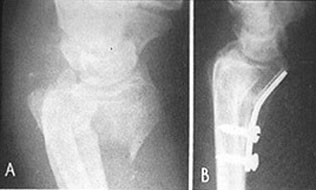

Smith's Fracture เป็นกระดูกหักที่ส่วนปลายของ radius พร้อมด้วย ventral angulation ของชิ้นส่วนปลาย ดังรูป sk 86

รูป sk 86    Smith's fracture A. แสดง  forward displacement ของกระดูก radius

B. แสดง การดามด้วย buttress plate ผู้ป่วยสามารถทำงานได้ใน 3 อาทิตย์